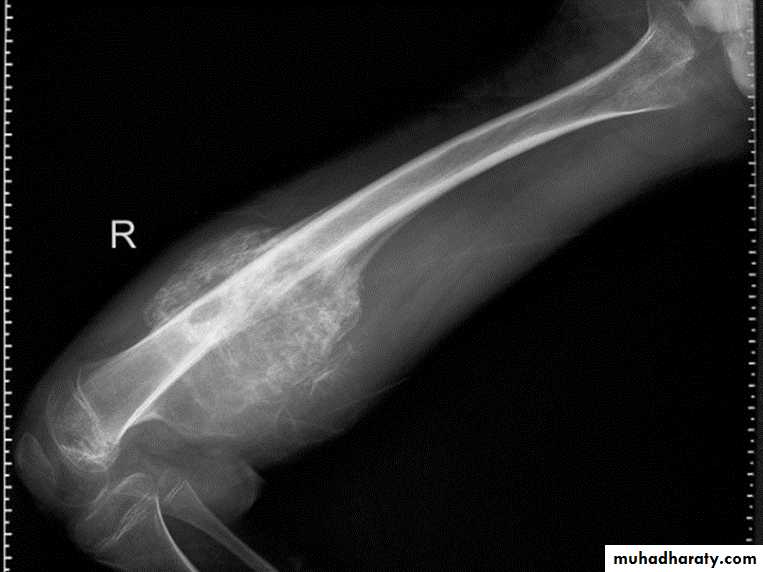

Fibrous dysplasia.

AP radiograph of the proximal femur showing a well-defined expanded lesion with typical ground-glass matrix mineralization and a thick, sclerotic margin .Fibrous dysplasia.

A multilocular, partly cystic, expansile lesion

of the midshaft femur is surrounded by a thick rim of reactive sclerosis.